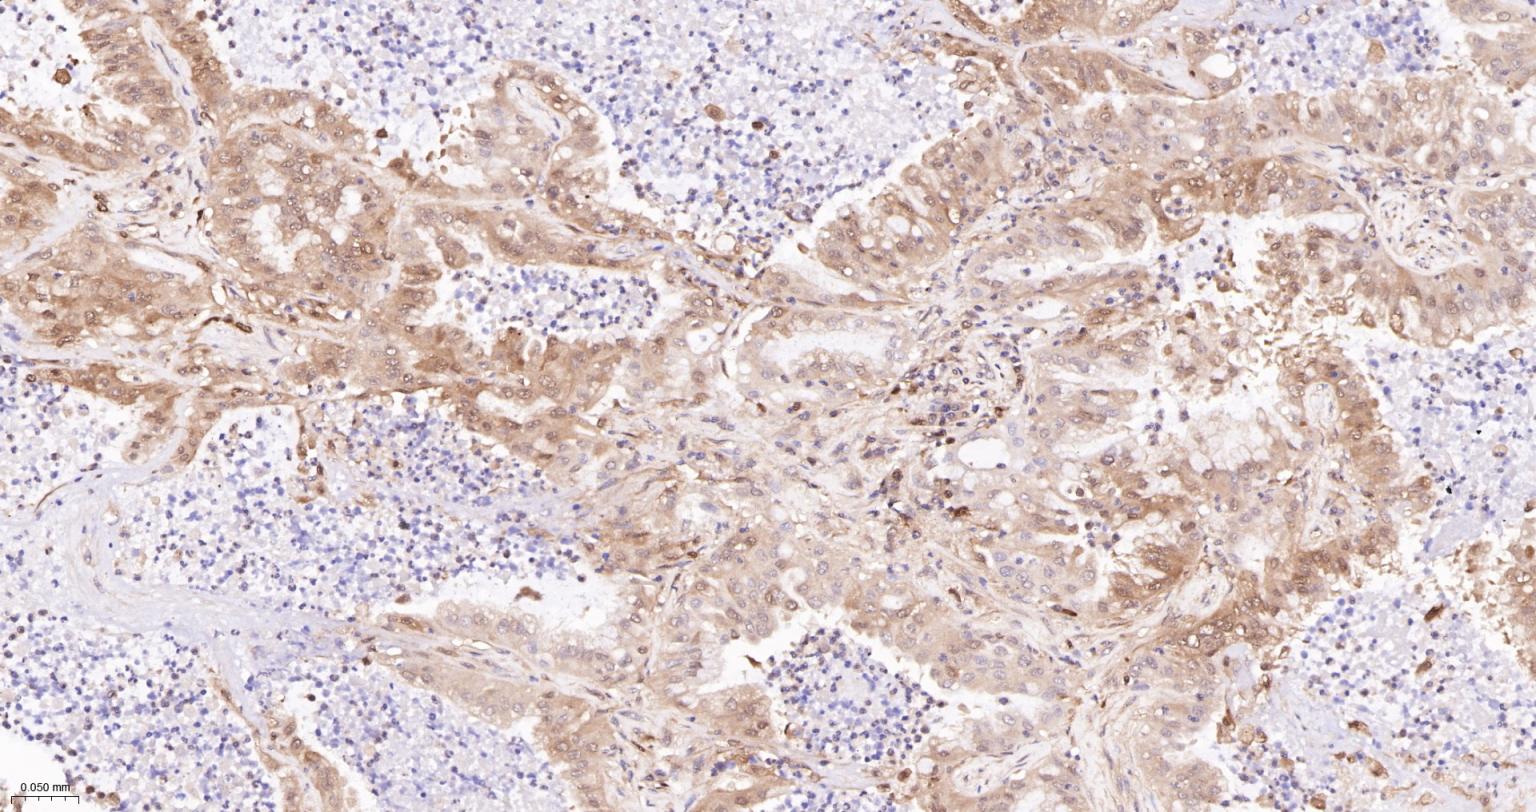

Paraformaldehyde-fixed, paraffin embedded Human Breast cancer; Antigen retrieval by boiling in sodium citrate buffer (pH6.0) for 15 min; Antibody incubation with GPX4 Monoclonal Antibody, Unconjugated(bsm-61552R) at 1:200 overnight at 4°C, followed by conjugation to the SP Kit(Rabbit, SP-0023) and DAB (C-0010) staining.

Paraformaldehyde-fixed, paraffin embedded Human lung cancer; Antigen retrieval by boiling in sodium citrate buffer (pH6.0) for 15 min; Antibody incubation with GPX4 Monoclonal Antibody, Unconjugated(bsm-61552R) at 1:200 overnight at 4°C, followed by conjugation to the SP Kit(Rabbit, SP-0023) and DAB (C-0010) staining.